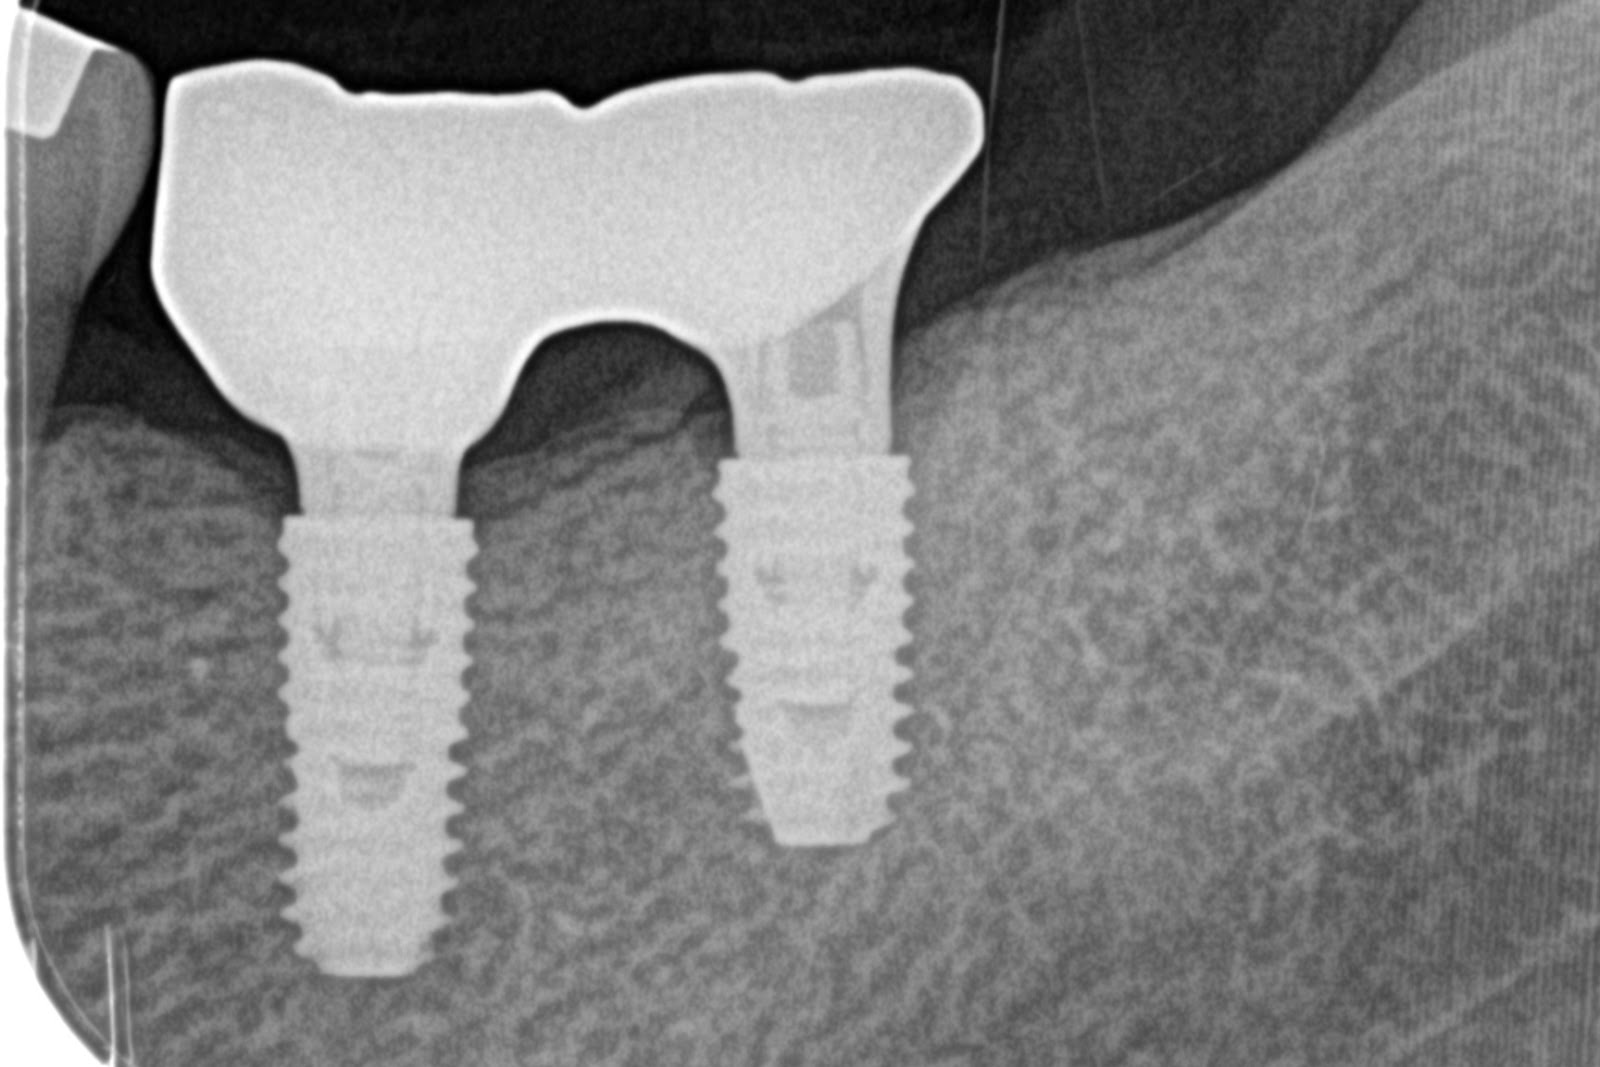

CASE-6左下の大臼歯部 インプラント埋入 2本

手術後

上部構造セット後

20~30年前に左下の奥歯を抜歯したとのことでしたが、入れ歯やインプラントといった補綴治療はせずに放置されている状態でした。

ご本人の希望もあり、左下の欠損部はインプラント治療を行うことになりました。

長年歯がない状態だったため、仮歯の期間を長めに取り、咬み合せ等の調整を重ねた上で上部構造の製作を行いました。 - 2

・インプラント埋入 2本